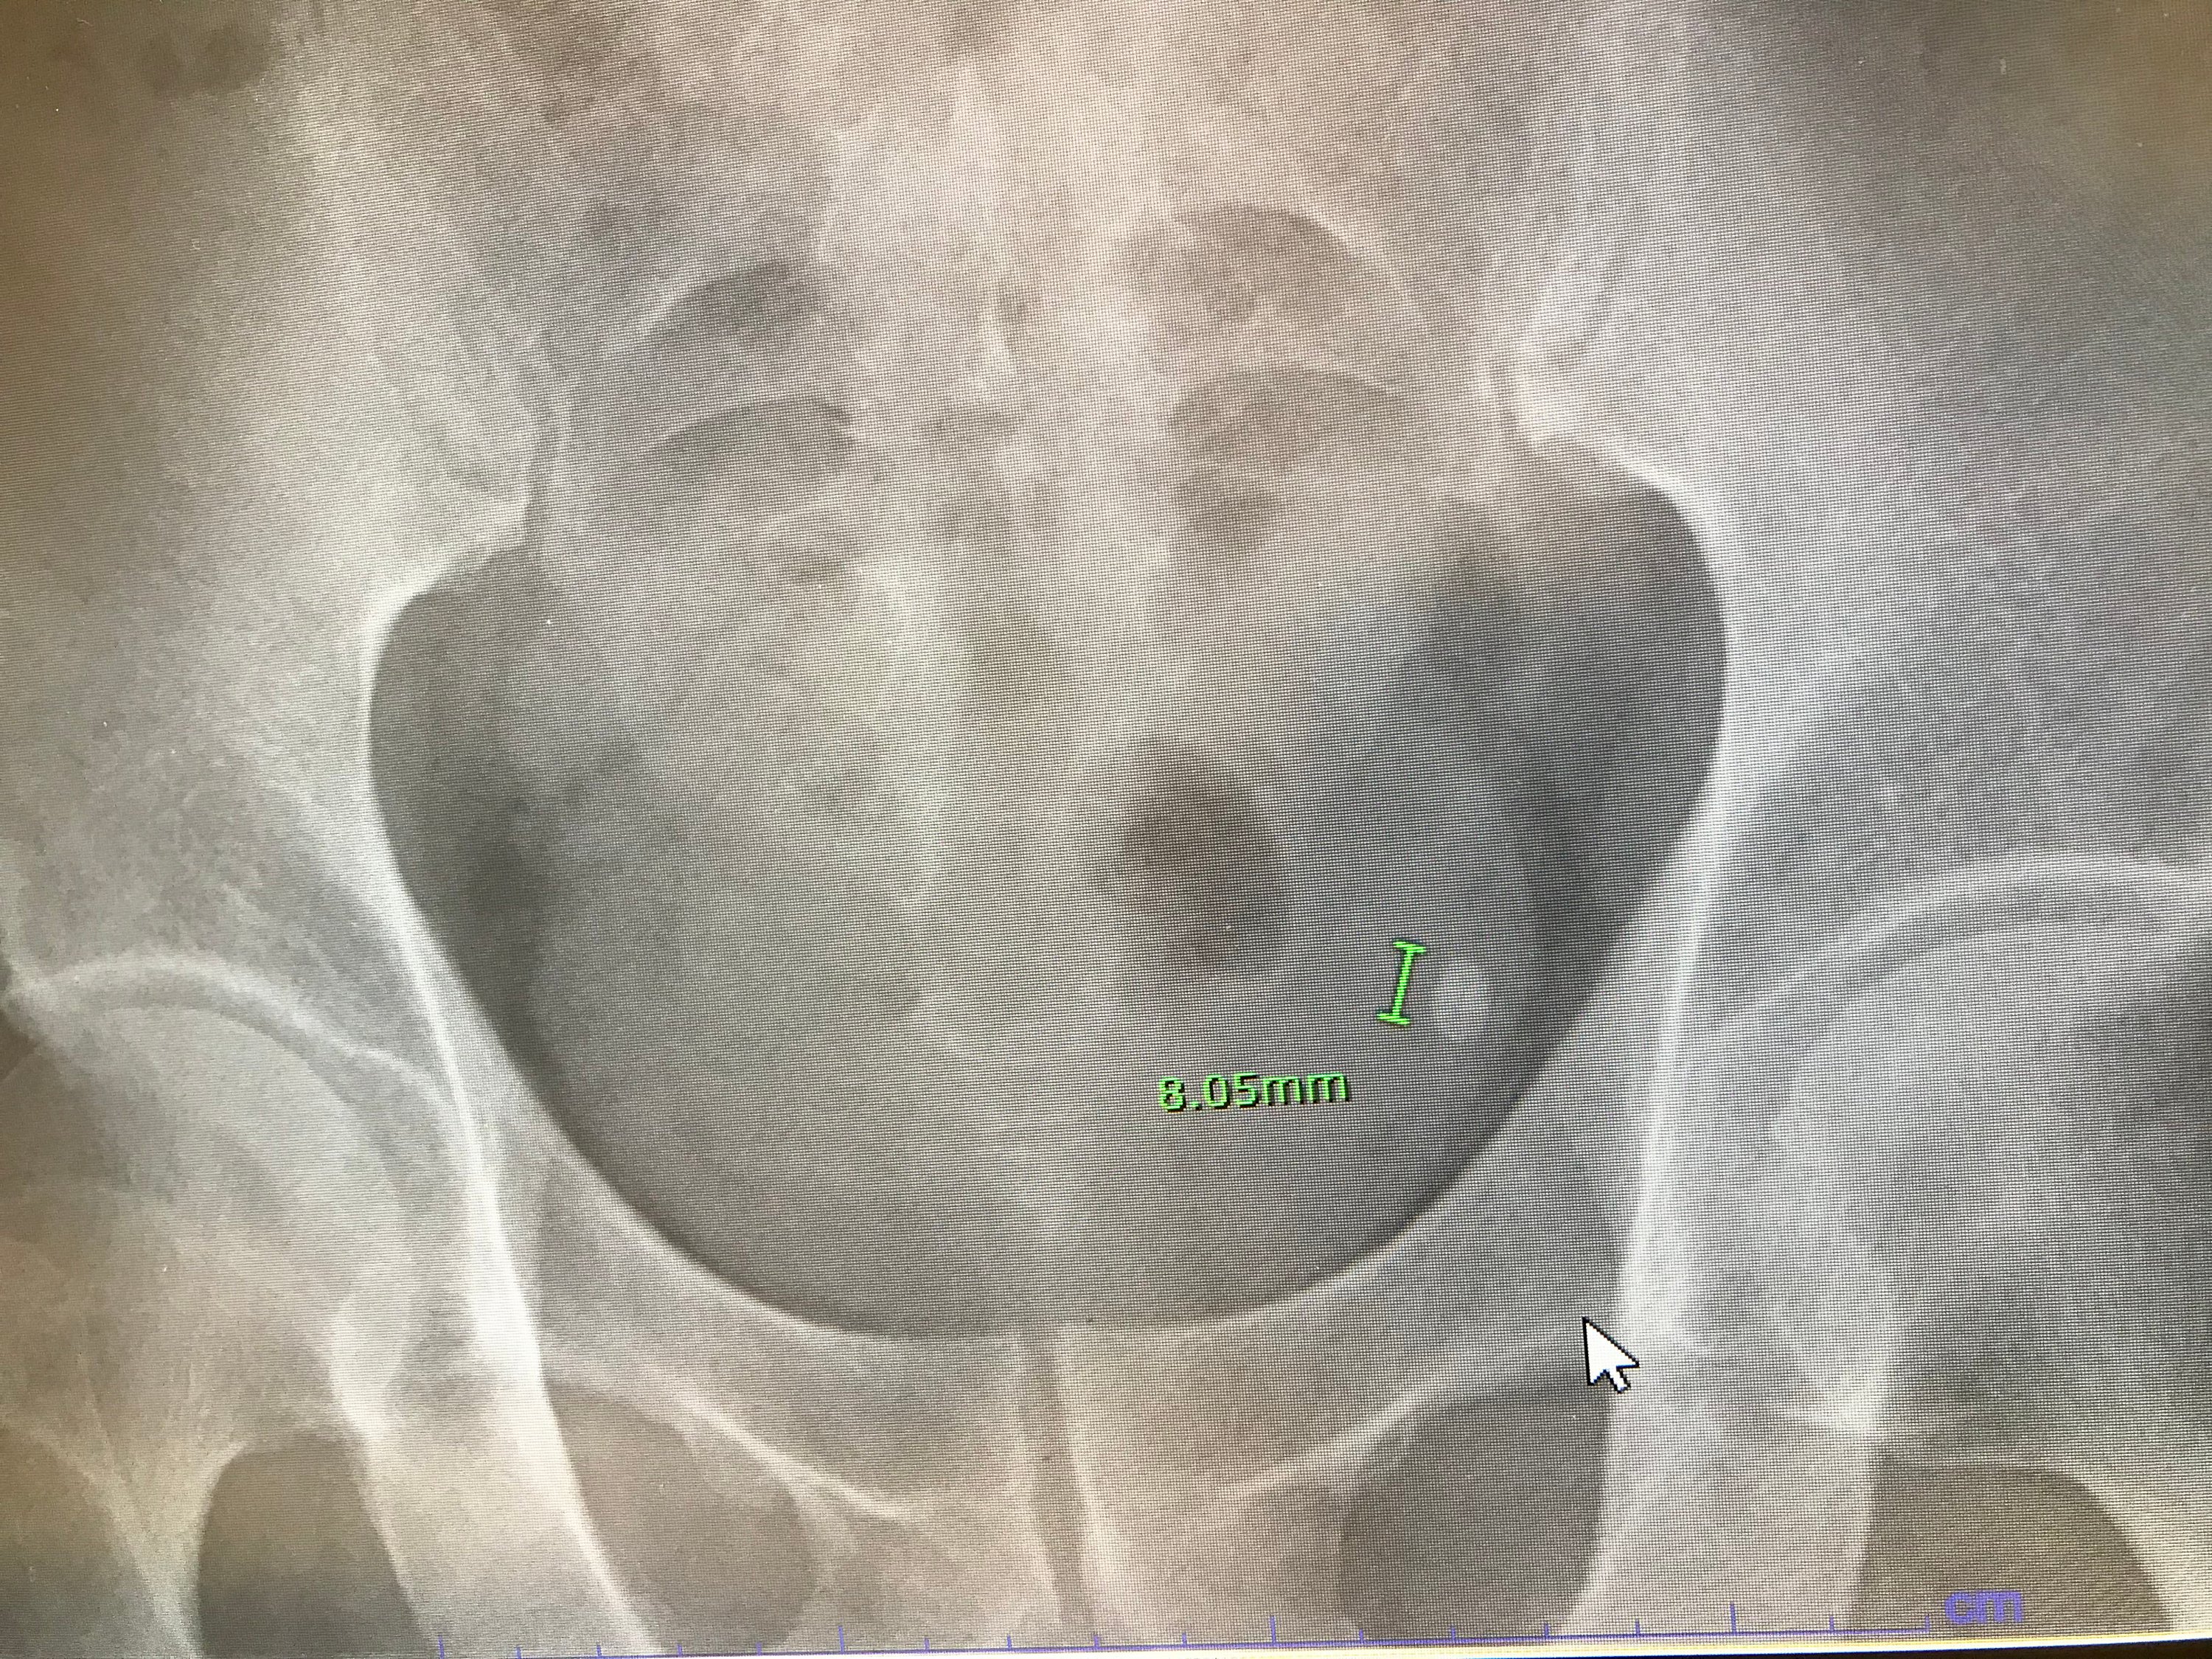

離島の診療所で検査すると、腎臓結石が尿路を降りているらしい。それが狭い部分で挟まって安定しているが、いずれは動き出して劇症化するので対処しないといけない。

何しろ内径1.6㎜の尿路を8㎜の結石が通過している。これで三度目の結石と戦うことになる。